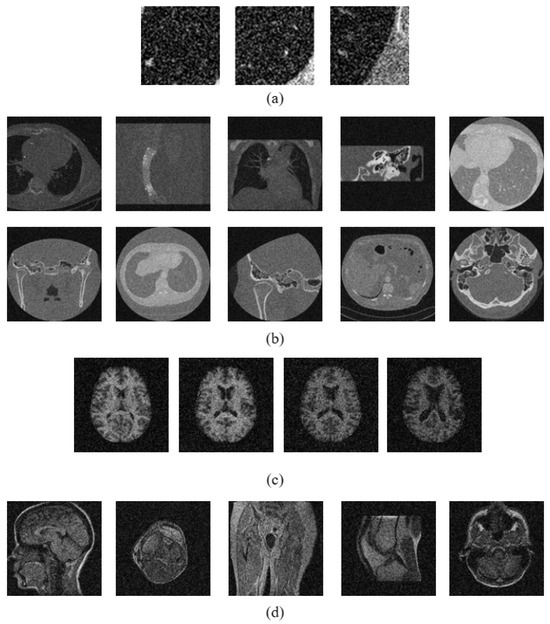

3.3. Dataset Description

| CT Image Datasets | MR Image Datasets | |||

|---|---|---|---|---|

| Emphysema CT | NEMA CT | OASIS MRI | NEMA MRI | |

| No. of Images | 168 | 600 | 416 | 372 |

| Image Size | 61 × 61 | 512 × 512 | 208 × 208 | 256 × 256 |

| No. of Classes | 3 | 10 | 4 | 5 |

| Images per Class | 59, 50, 59 | 54, 70, 66, 50, 15 | 125, 104, 91, 96 | 72, 100, 76, 59, 65 |

| 60, 52, 104, 60, 69 | ||||